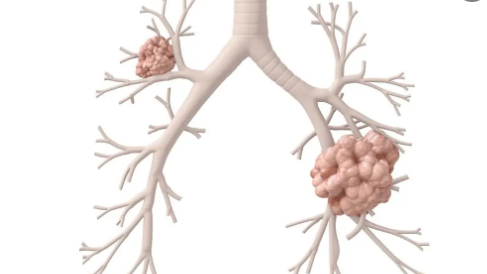

对于抽烟人群来说,患上肺癌的几率还是挺高的,但为什么不抽烟也可能得肺癌呢?因为形成肺癌的因素很多,并不单单只是因为抽烟这个原因。所以,肺癌是怎么一步一步形成的?一起来看看生活百科网带来的介绍吧!

肺癌的病因至今尚不完全清楚,导致肺癌发生的因素很多。首先,长期大量吸烟是肺癌的重要致病因素。如果连续多年每天吸烟40支以上,肺鳞状细胞癌和小细胞肺癌的发病率是不吸烟者的近10倍。

因此,戒烟对于预防肺癌很重要。手段之一。其次,长期接触石棉、铬、铜、砷等重金属和放射性物质的人,易患肺癌。空气污染和烟尘中的致癌物也是肺癌的诱发因素,因此控制环境非常重要。此外,人体的内部因素,如身体的免疫状况、遗传因素、慢性肺部感染等,也可能增加患肺癌的风险。近年来,研究还发现,人体自身的基因变化也与肺癌的发病有关。